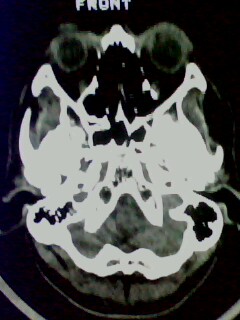

以下是引用随光逐影在2009-5-20 19:22:00的发言:[br]1)考虑左上颌骨近中线区含牙囊肿。2)鼻中隔右突偏曲。3)双侧下鼻甲肥大。

以下是引用余辉在2009-5-20 19:35:00的发言:[br]1)考虑左上颌骨近中线区含牙囊肿。2)鼻中隔右突偏曲。3)双侧下鼻甲肥大。[br]支持,不除外上颌骨正中囊肿,有窦道通鼻前庭,出血可能是内部有感染,图像不是很清,可照个片看一下